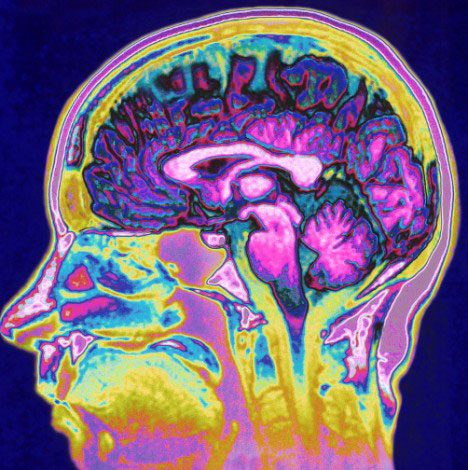

An image of a brain scan. Source: DailyMail